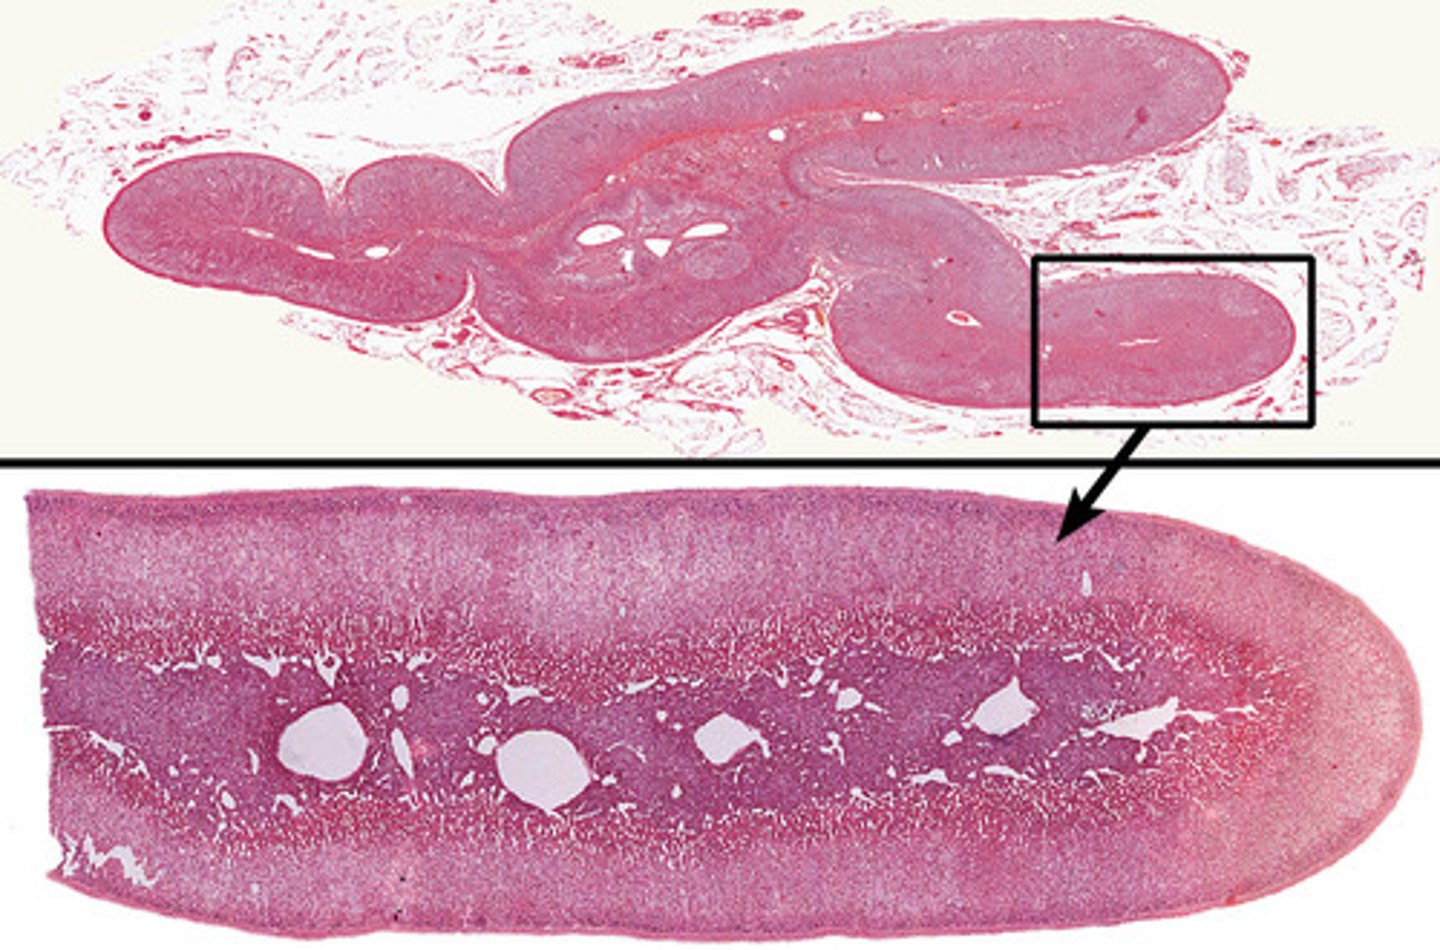

Adrenal gland

Adrenal cortex

Zona glomerulosa

Zona fasciculata

Zona reticularis

Adrenal medulla